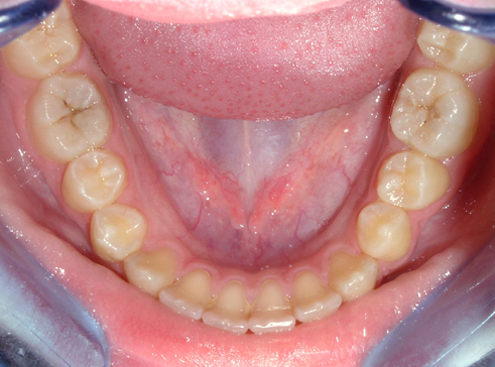

Obr. 2. Dolní zubní oblouk se zubním kamenem interdentálně mezi dolními řezáky